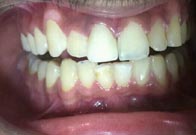

(6) Teeth Whitening

Before Treatment

After Treatment

Patient reported to us with the concern of Yellow teeth. Patient was conscious in social gatherings due to lack of confidence. Complete gum treatment and polishing was done for the patient followed by in office bleaching to achieve 2 shade whiter teeth. Home kit was a also delivered to the patient for maintenance as patient was coming from far.